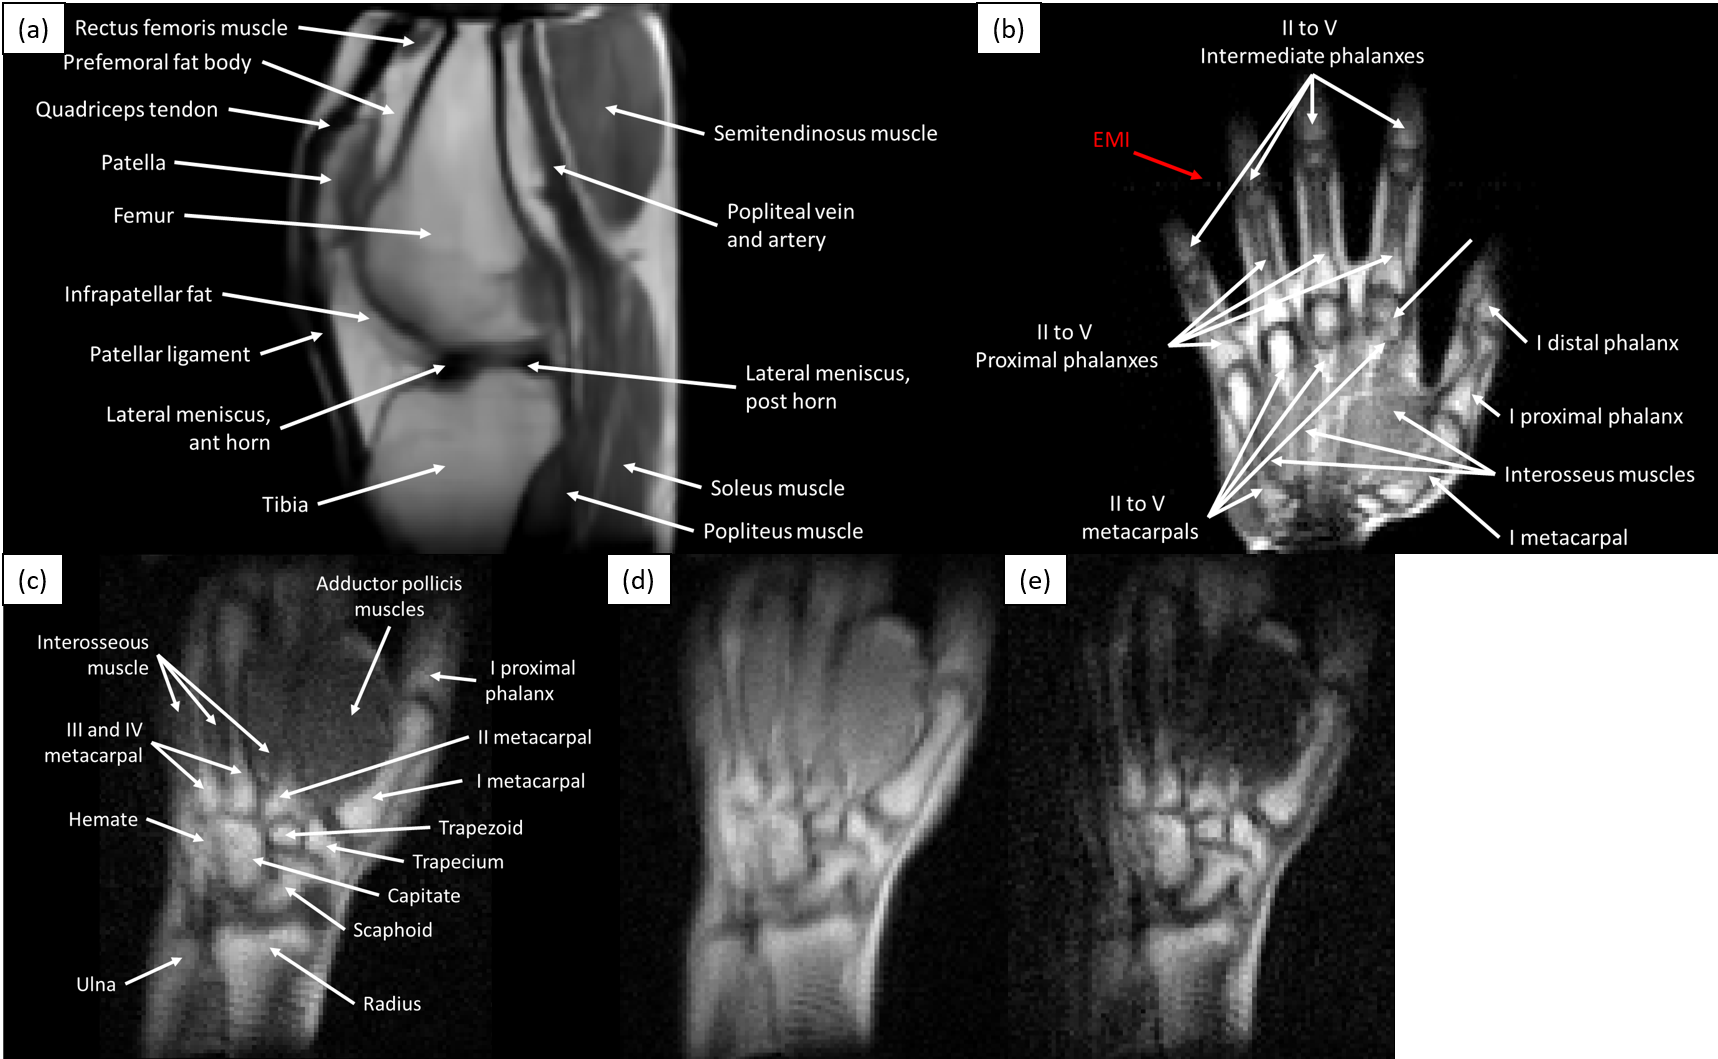

Figure 2: Single slices of 3D-TSE in vivo acquisitions of different volunteers in the MRI physics laboratory: (a) T1subscript𝑇1T_{1}-weighted image of a knee, acquired in 19 min, with BM4D filtering and ×2absent2\times 2 rescaling; (b) T1subscript𝑇1T_{1}-weighted image of a hand (10 min), without post-processing, with a faint EMI line visible along the phase-encoded direction; (c)-(e) T1subscript𝑇1T_{1}, ρ𝜌\rho and T2subscript𝑇2T_{2}-weighted images of a wrist (12 min).

The images in Fig. 2 show the scanner performance in the laboratory. They correspond to in vivo 3D-TSE acquisitions of different healthy subjects on different days, showing selected slices of a left knee, a right hand and a right wrist. Acquisition times ranged from 10 to 19 min (Methods). All images show sufficient tissue contrast and spatial resolution to identify relevant anatomical features, including muscles, fat, cortical bone, bone marrow, tendons, ligaments, veins, arteries and fascia. In these images we show different contrast mechanisms17, with weightings on T1subscript𝑇1T_{1}, T2subscript𝑇2T_{2} and proton density (ρ𝜌\rho). The knee image in Fig. 2(a) is BM4D-filtered37 and rescaled to increase the number of pixels by a factor of ×2absent2\times 2, whereas the hand in Fig. 2(b) is unprocessed after Fourier reconstruction and weak EMI effects result in a faint line along the horizontal (phase-encoded) direction.

The knee image in Fig. 2(a) was acquired with a T1subscript𝑇1T_{1}-weighted 3D-TSE sequence, with FoV=130×140×180FoV130140180\text{FoV}=130\times 140\times 180 mm3, a pixel resolution of 1.85×1.75×21.851.7521.85\times 1.75\times 2 mm3, ETL=5ETL5\text{ETL}=5, TE=20TE20\text{TE}=20 ms, TR=200TR200\text{TR}=200 ms, BW=17.5BW17.5\text{BW}=17.5 kHz, and 4 averages for a total scan time of 19.2 min. The duration of resonant π/2𝜋2\pi/2 and π𝜋\pi-pulses in all images are 40 µsabsenttimes40µs\approx$40\text{\,}\mathrm{\SIUnitSymbolMicro}\mathrm{s}$ and 80 µsabsenttimes80µs\approx$80\text{\,}\mathrm{\SIUnitSymbolMicro}\mathrm{s}$, respectively, and dephasing gradient pulses after the RF pulses are pre-emphasized by a factor 1.006absent1.006\approx 1.006 to place the echoes at the center of the data acquisition windows.

The hand image in Fig. 2(b) was acquired with a T1subscript𝑇1T_{1}-weighted 3D-TSE sequence, with FoV=180×180×50FoV18018050\text{FoV}=180\times 180\times 50 mm3, a pixel resolution of 1.5×1.5×51.51.551.5\times 1.5\times 5 mm3, ETL=10ETL10\text{ETL}=10, TE=20TE20\text{TE}=20 ms, TR=400TR400\text{TR}=400 ms, BW=30BW30\text{BW}=30 kHz, and 13 averages for a total scan time of 10.4 min.

The wrist image in Fig. 2(c) was acquired with a T1subscript𝑇1T_{1}-weighted 3D-TSE sequence, with FoV=180×140×80FoV18014080\text{FoV}=180\times 140\times 80 mm3, a pixel resolution of 1.5×1.5×101.51.5101.5\times 1.5\times 10 mm3, ETL=3ETL3\text{ETL}=3, TE=20TE20\text{TE}=20 ms, TR=100TR100\text{TR}=100 ms, BW=30BW30\text{BW}=30 kHz, and 30 averages for a total scan time of 12 min.

The wrist image in Fig. 2(d) was acquired with a ρ𝜌\rho-weighted 3D-TSE sequence, with FoV=180×140×80FoV18014080\text{FoV}=180\times 140\times 80 mm3, a pixel resolution of 1.5×1.5×101.51.5101.5\times 1.5\times 10 mm3, ETL=5ETL5\text{ETL}=5, TE=20TE20\text{TE}=20 ms, TR=1000TR1000\text{TR}=1000 ms, BW=30BW30\text{BW}=30 kHz, and 5 averages for a total scan time of 12 min.

The wrist image in Fig. 2(e) was acquired with a T2subscript𝑇2T_{2}-weighted 3D-TSE sequence, with FoV=180×140×80FoV18014080\text{FoV}=180\times 140\times 80 mm3, a pixel resolution of 1.5×1.5×101.51.5101.5\times 1.5\times 10 mm3, ETL=5ETL5\text{ETL}=5, echo spacing of 20 ms, effective TE=100TE100\text{TE}=100 ms, TR=1000TR1000\text{TR}=1000 ms, BW=30BW30\text{BW}=30 kHz, and 5 averages for a total scan time of 12 min.